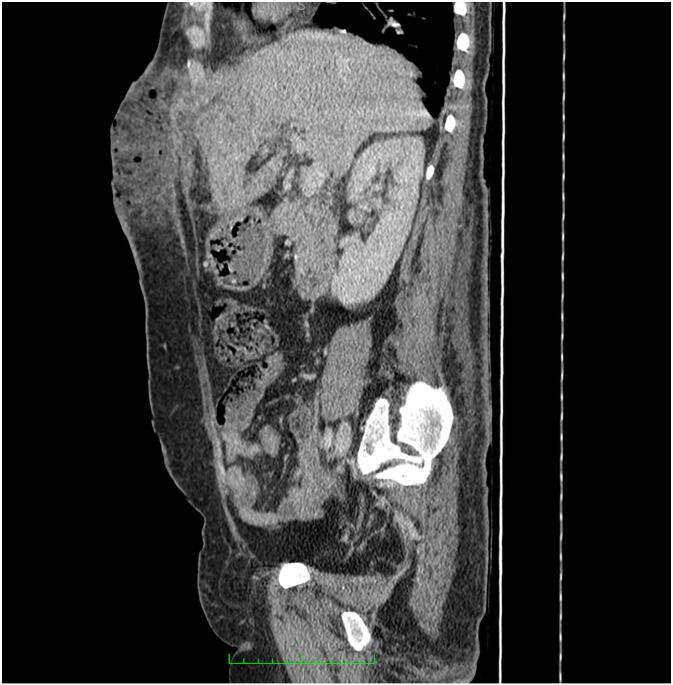

Contrast-enhanced abdominal CT revealed two subcapsular collections in segment III of the liver, measuring 28 × 12 mm and 27 × 14 mm, each with fistulous tracts to the anterior abdominal wall. These extended over 29 mm and 34 mm, respectively, and were associated with extensive subcutaneous soft tissue infiltration, poorly defined necrotic areas spanning more than 10 cm in height, and the presence of subcutaneous emphysematous bullae suggestive of necrotizing fasciitis [Fig. 3, Fig. 4]. Additionally, intra- and extrahepatic biliary dilatation was noted upstream of multiple stones in the common bile duct.

Fig. 4.

CT image (sagittal view) illustrating extensive soft tissue gas infiltration and necrosis involving the abdominal wall consistent with necrotizing fasciitis.

The clinical presentation of necrotizing fasciitis can be nonspecific in its early stages, often mimicking cellulitis or abscess. However, the presence of rapidly spreading erythema, crepitus, disproportionate pain, systemic toxicity, and soft tissue gas on imaging should raise strong suspicion [8,9]. In our case, contrast-enhanced CT provided key diagnostic information, revealing hepatic subcapsular abscesses with fistulous communication, soft tissue necrosis, and emphysematous changes consistent with necrotizing fasciitis.